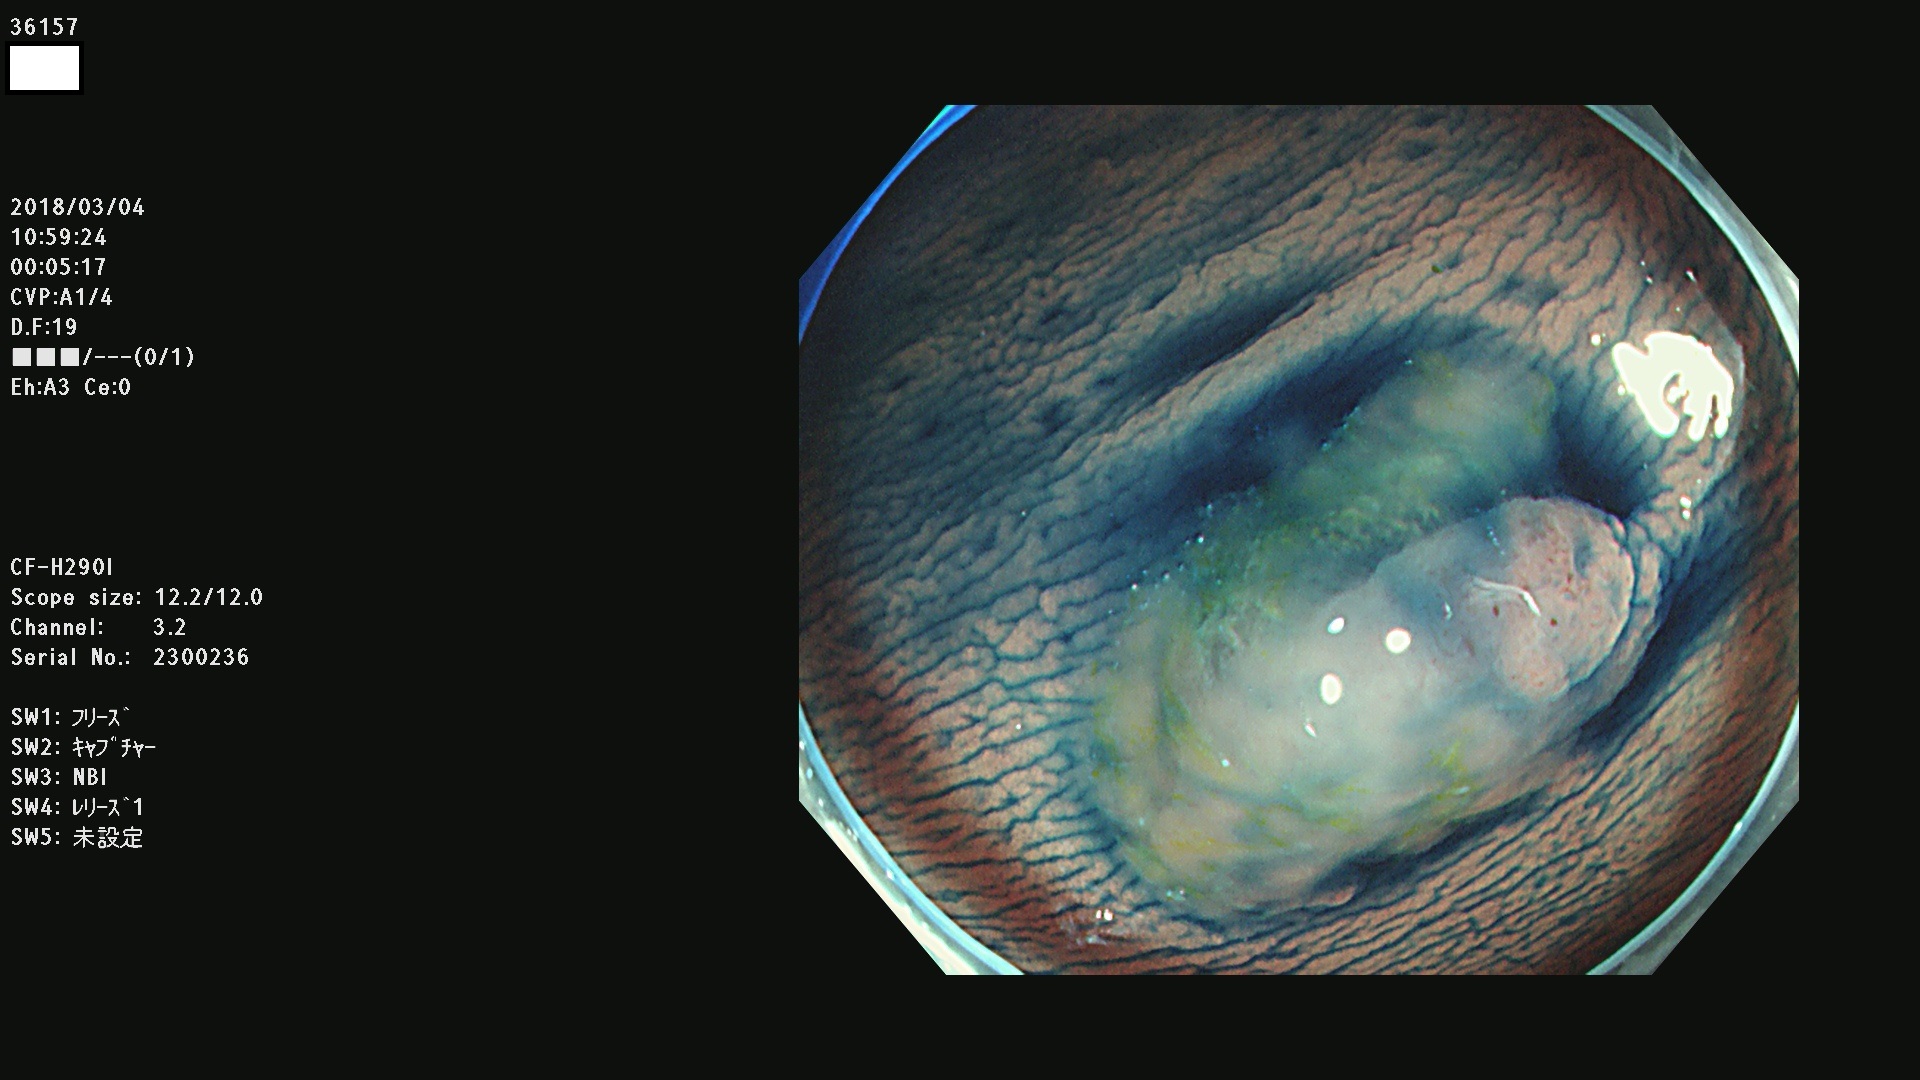

腺腫発見率57 % (カルテ番号 36100〜36199の100名の方の検査結果で集計)大腸癌検診最新情報

以下のカルテ番号の方に腺腫(Adenoma,Group3〜5)が見つかりました(集計法)

36100 36101 36102 36103 36104 36105 36107 36108 36110 36111 36114 36115 36117 36119 36120 36122 36125 36127 36129(SSA/Pのみ) 36133 36135 36137 36138 36139 36143 36144 36146 36147 36152 36153 36154 36155 36157(SSA/Pのみ) 36158 36162 36163 36165 36167 36169 36170 36173 36174 36176 36177 36178 36179 36180 36183 36185 36187 36189 36190(SSA/Pのみ) 36191 36193 36195(SSA/Pのみ) 36197(SSA/Pのみ) 36199(SSA/Pのみ)

発見困難で危険性の高い平坦型病変(上記100名より抽出) ![]()